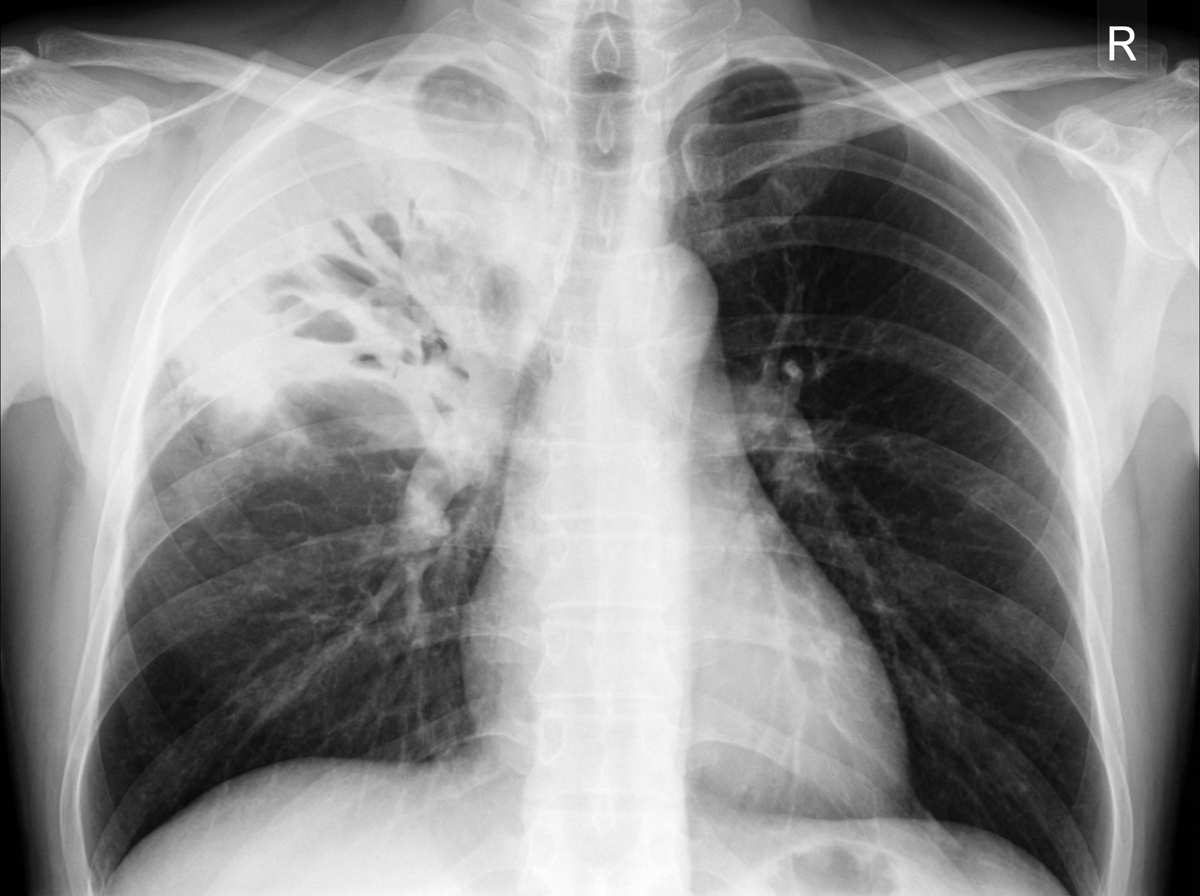

A 67-year-old woman is brought to the emergency department for evaluation of fever, chest pain, and a cough that has produced a moderate amount of greenish-yellow sputum for the past 2 days. During this period, she has had severe malaise, chills, and difficulty breathing. Her past medical history is significant for hypertension, hypercholesterolemia, and type 2 diabetes, for which she takes lisinopril, atorvastatin, and metformin. She has smoked one pack of cigarettes daily for 20 years. Her vital signs show her temperature is 39.0°C (102.2°F), pulse is 110/min, respirations are 33/min, and blood pressure is 143/88 mm Hg. Pulse oximetry on room air shows an oxygen saturation of 94%. Crackles are heard on auscultation of the right upper lobe. Laboratory studies show a leukocyte count of 12,300/mm3, an erythrocyte sedimentation rate of 60 mm/h, and urea nitrogen of 15 mg/dL. A chest X-ray is shown. Which of the following is the most appropriate next step to manage this patient’s symptoms?